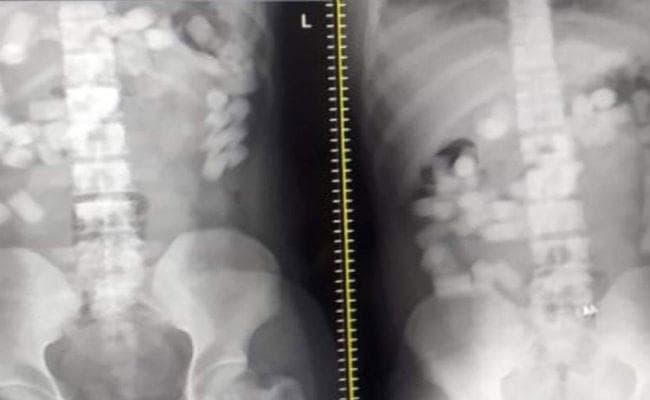

सामान से कुछ नहीं मिलने पर इनको स्कैनिंग और एक्स-रे के लिए भेजा गया. इन सबके पेट में ड्रग्स वाली कैप्सूल दिखीं. इन्हें निकलवाने के लिए नारकोटिक्स ब्यूरो के अधिकारियों ने लगभग 10 दर्जन केले खिलाये.